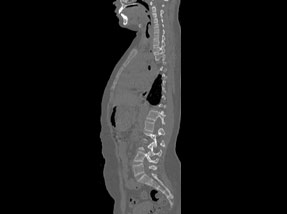

• Pre-SurgeryBefore

• Post SurgeryAfter

Case 1